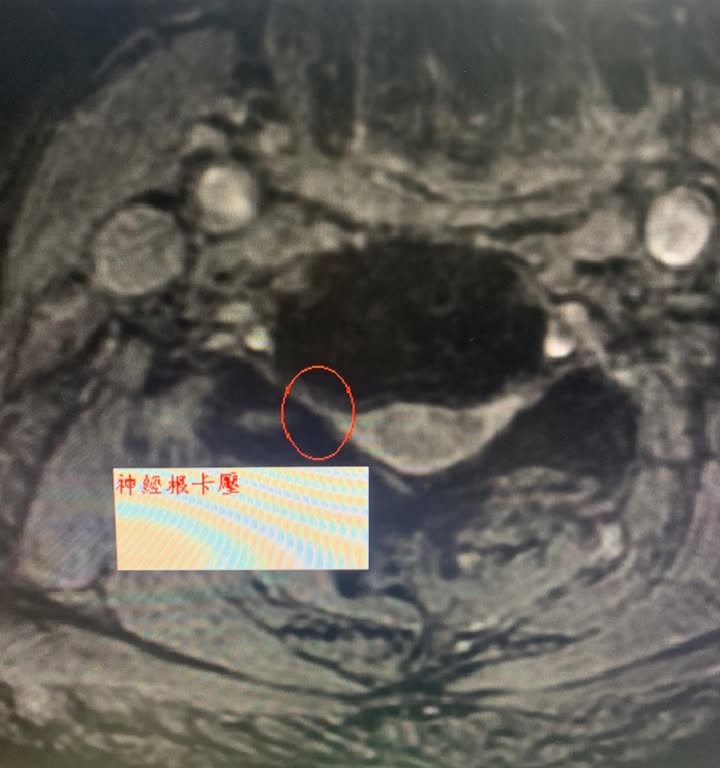

😢68歲的大學教授林伯伯最近這兩個多月右邊頸椎痛連上臂,復健去了快二十次,效果不如預期,只好去家中附近的醫學中心拍片檢查頸椎MRI,証實C5神經根卡壓,晚上常常發生肩膀痠痛醒來的情況,原本想說吃止痛藥休息,跟拉脖子就好,結果情況一直惡化,最後痛到手肘來,一直在刺痛,轉脖子向右邊非常的卡,也不太能向前屈,骨科醫師建議開刀,因為復健已經快兩個月仍然沒特別大的效果